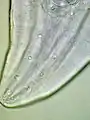

| Male Gongylonema pulchrum as seen under a light microscope.[1] | |

The morphology of the worm is as follows, from a 2000 Veterinary Medicine study: "The anterior end in both sexes was covered by numerous cuticular platelets. There was a pair of lateral cervical papillae. The buccal opening was small and extended in the dorsoventral direction. Around the mouth a cuticular elevation enclosed the labia, and eight papillae were located laterodorsally and lateroventrally. Two large lateral amphids were seen. On the lateral sides of the female's tail, phasmidal apertures were observed. The caudal end of the male was asymmetrically alate and bore 10 pairs of papillae and two phasmidal apertures."[3] The average length for male worms is 29.1 mm (1.15 in), while the average length for adult females is 58.7 mm (2.31 in). The worm is highly mobile, as observed in patients’ mouths and as evidenced by the morphological design of the worm.